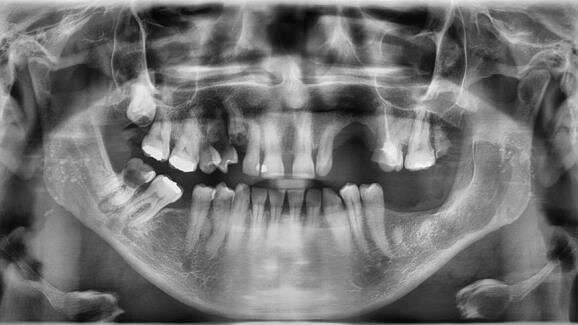

Badaniem objęto 40 pacjentów w wieku 15-79 lat (18 kobiet i 22 mężczyzn, średnia wieku 34.8 lat) z terenu województw śląskiego i kujawsko-pomorskiego. Do grupy badanej włączono 20 chorych (10 kobiet i 10 mężczyzn) w wieku 15-78, średnia wieku 33.4 lat. Grupę kontrolną utworzyło także 20 osób (9 kobiet i 11 mężczyzn) w wieku 21-79 lat (średnia wieku 35.3 lat). W grupie badanej, po wyłuszczeniu torbieli zastosowano PRP w połączeniu z gąbką kolagenową. W grupie kontrolnej zastosowano PRP w połączeniu z różnymi biomateriałami. Do obu grup zakwalifikowano osoby z wstępnie rozpoznanymi klinicznie i radiologicznie torbielami zębopochodnymi.

_radiologicznie stwierdzone jednokomorowe ogniska osteolityczne kości szczęk lub żuchwy o średnicy powyżej 10 mm z pobraniem wycinka i BAC w celu potwierdzenia obrazu wstępnego rozpoznania,

Po wstępnej ocenie klinicznej i radiologicznej zmian wykonywano BAC i pobranie wycinka próbnego w znieczuleniu miejscowym. Otrzymane potwierdzenie charakteru zmiany warunkowało planowanie leczenie chirurgicznego w warunkach ambulatoryjnych. Po uzyskaniu zgody pacjentów na pobranie krwi i użycie materiału rekonstrukcyjnego przeprowadzano planowe zabiegi cystektomii metodą Partsch II w znieczuleniu miejscowym oraz 2 zabiegi w znieczuleniu ogólnym z intubacją ustno-tchawiczą. Charakterystykę obu grup przedstawiono w formie zbiorczej w tabelach 1-3.

Uzyskane wyniki badań histopatologicznych przedstawiono w formie zbiorczej na rycinie 1. Przykłady leczonych torbieli i przebiegu procesów gojenia oraz mikrofotografie przedstawiono na rycinach 2-25.

W analizie histopatologicznej ze standardowym barwieniem hematoksyliną i eozyną uzyskano w grupie badanej potwierdzenie usunięcia 5 torbieli zawiązkowych i 15 korzeniowych. W grupie kontrolnej wykazano obecność 2 torbieli zawiązkowych i 18 korzeniowych.